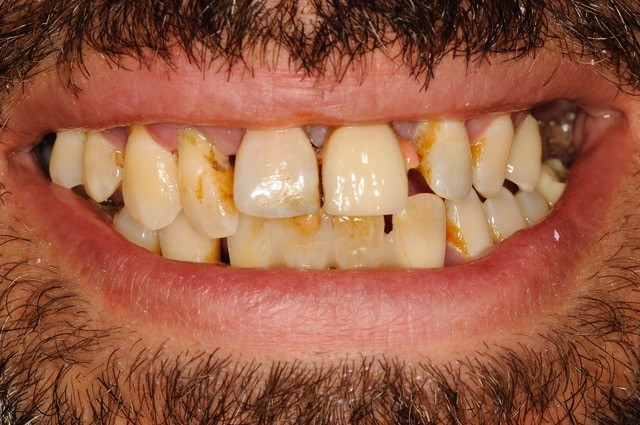

Situazione iniziale

Paziente molto giovane e cambio estetico molto importante, con altrettanto importante resettiva ossea del mascellare superiore.